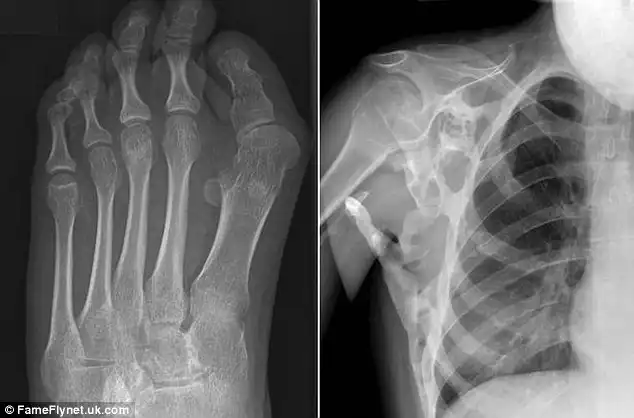

17-летняя девушка из Западного Лондона страдает от прогрессирующей оссифицирующей фибродисплазии (ПОФ) — болезни, которая превращает ее мышцы и сухожилия в кости. Из-за того, что в плече у Шони выросла дополнительная кость, девушка не может поднять руки выше талии. Она даже не в состоянии самостоятельно почистить зубы, помыть волосы или одеть платье, а для того, чтобы сделать прическу, Шони приходится использовать специальные щипцы и расческу с удлиненной ручкой. При этом ее состояние может стать еще хуже.